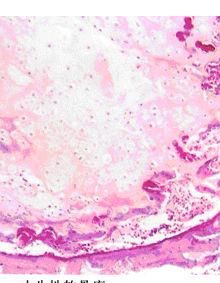

肉眼切面呈淡藍色或銀白色,半透明,可有鈣化或囊性變。鏡下見瘤組織由成熟透明軟骨組成,呈不規則分葉狀。位於盆骨、胸骨、肋骨、四肢長骨或椎骨的軟骨瘤易惡變;發生在指(趾)骨的軟骨瘤極少惡變。[1]